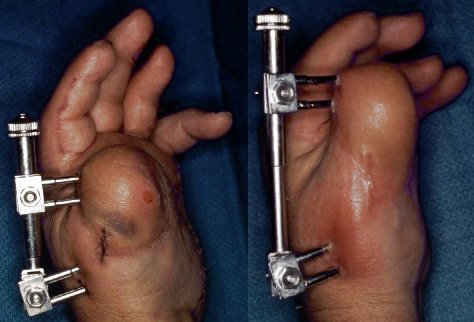

The thumb was lengthened over a period of six weeks with an external fixator.

Interim result. Flap debulking has since been performed.